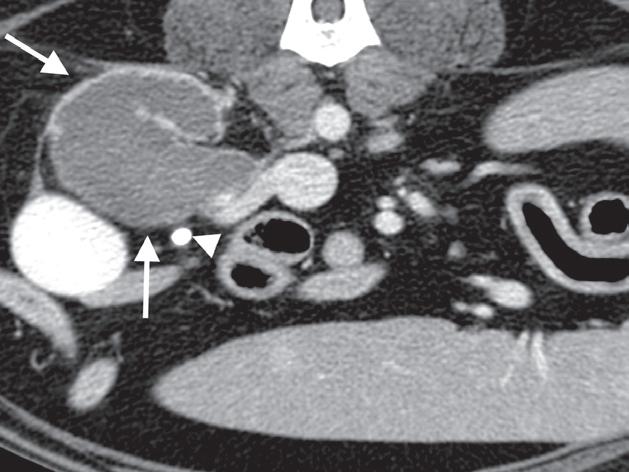

Badanie wykonano u 7-letniego rottweilera z rozpoznanym guzem nadnercza oraz nagłymi objawami dyskomfortu jamy brzusznej. Obrazy na ryc. a–c uporządkowano od strony doczaszkowej do doogonowej. Nadnercze prawe jest powiększone (a, d – otwarty grot strzałki) i ma widoczną ekscentryczną komponentę torbielowatą o densyjności płynu, która rozchodzi się doogonowo (a, b – strzałki). Tkanka miękka rozrostu oraz torebka nadnercza wykazują obwodowe wzmocnienie pokontrastowe. Torbielowata komponenta zmiany rozrostowej widoczna na obrazie odpowiada krwotokowi, który rozciąga się doogonowo w przestrzeni zaotrzewnowej (d). Dobrzusznie od zmiany widoczny jest moczowód (b – grot strzałki). Diagnoza makroskopowa i histologiczna została potwierdzona po chirurgicznym usunięciu zmiany (e – strzałka). Proszę zwrócić uwagę na porównanie obrazu TK zmiany (d) z wyciętym preparatem makroskopowym (f)